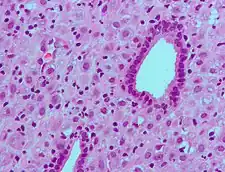

Metabolism

The metabolism of progesterone is rapid and extensive and occurs mainly in the liver,[112][113][114] though enzymes that metabolize progesterone are also expressed widely in the brain, skin, and various other extrahepatic tissues.[77][115] Progesterone has an elimination half-life of only approximately 5 minutes in circulation.[112] The metabolism of progesterone is complex, and it may form as many as 35 different unconjugated metabolites when it is ingested orally.[114][116] Progesterone is highly susceptible to enzymatic reduction via reductases and hydroxysteroid dehydrogenases due to its double bond (between the C4 and C5 positions) and its two ketones (at the C3 and C20 positions).[114]

The major metabolic pathway of progesterone is reduction by 5α-reductase[77] and 5β-reductase into the dihydrogenated 5α-dihydroprogesterone and 5β-dihydroprogesterone, respectively.[113][114][117][118] This is followed by the further reduction of these metabolites via 3α-hydroxysteroid dehydrogenase and 3β-hydroxysteroid dehydrogenase into the tetrahydrogenated allopregnanolone, pregnanolone, isopregnanolone, and epipregnanolone.[119][113][114][117] Subsequently, 20α-hydroxysteroid dehydrogenase and 20β-hydroxysteroid dehydrogenase reduce these metabolites to form the corresponding hexahydrogenated pregnanediols (eight different isomers in total),[113][118] which are then conjugated via glucuronidation and/or sulfation, released from the liver into circulation, and excreted by the kidneys into the urine.[112][114] The major metabolite of progesterone in the urine is the 3α,5β,20α isomer of pregnanediol glucuronide, which has been found to constitute 15 to 30% of an injection of progesterone.[17][120] Other metabolites of progesterone formed by the enzymes in this pathway include 3α-dihydroprogesterone, 3β-dihydroprogesterone, 20α-dihydroprogesterone, and 20β-dihydroprogesterone, as well as various combination products of the enzymes aside from those already mentioned.[17][114][120][121] Progesterone can also first be hydroxylated (see below) and then reduced.[114] Endogenous progesterone is metabolized approximately 50% into 5α-dihydroprogesterone in the corpus luteum, 35% into 3β-dihydroprogesterone in the liver, and 10% into 20α-dihydroprogesterone.[122]

Relatively small portions of progesterone are hydroxylated via 17α-hydroxylase (CYP17A1) and 21-hydroxylase (CYP21A2) into 17α-hydroxyprogesterone and 11-deoxycorticosterone (21-hydroxyprogesterone), respectively,[116] and pregnanetriols are formed secondarily to 17α-hydroxylation.[123][124] Even smaller amounts of progesterone may be also hydroxylated via 11β-hydroxylase (CYP11B1) and to a lesser extent via aldosterone synthase (CYP11B2) into 11β-hydroxyprogesterone.[125][126][44] In addition, progesterone can be hydroxylated in the liver by other cytochrome P450 enzymes which are not steroid-specific.[127] 6β-Hydroxylation, which is catalyzed mainly by CYP3A4, is the major transformation, and is responsible for approximately 70% of cytochrome P450-mediated progesterone metabolism.[127] Other routes include 6α-, 16α-, and 16β-hydroxylation.[114] However, treatment of women with ketoconazole, a strong CYP3A4 inhibitor, had minimal effects on progesterone levels, producing only a slight and non-significant increase, and this suggests that cytochrome P450 enzymes play only a small role in progesterone metabolism.[128]

Metabolism of progesterone in humans[129]